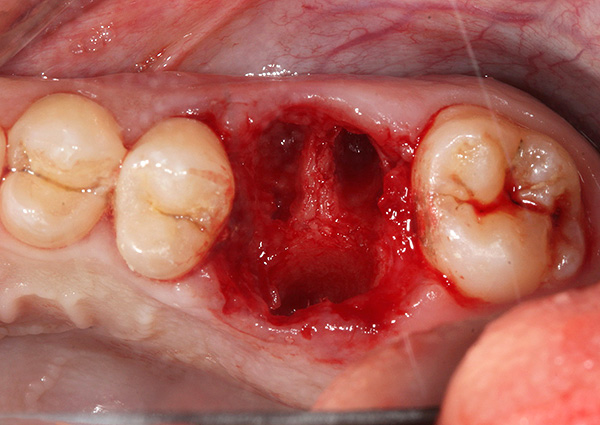

Foto di un dente le cui radici sono separate da un trapano prima della rimozione: